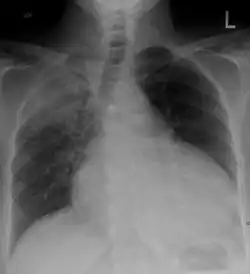

Chest x-ray: is non-specific and may not help identify a pericardial effusion but a very large, chronic effusion can present as "water-bottle sign" on an x-ray, which occurs when the cardiopericardial silhouette is enlarged and assumes the shape of a flask or water bottle.[2] Chest radiograph is also helpful in ruling out pneumothorax, pneumonia, and esophageal rupture.

A large anechoic (black) pericardial effusion as seen on ultrasound. Closed arrow: the heart, open arrow: the effusion - Pericardial effusion due to malignancy. Note bulbous heart and primary lung cancer in right upper lobe.